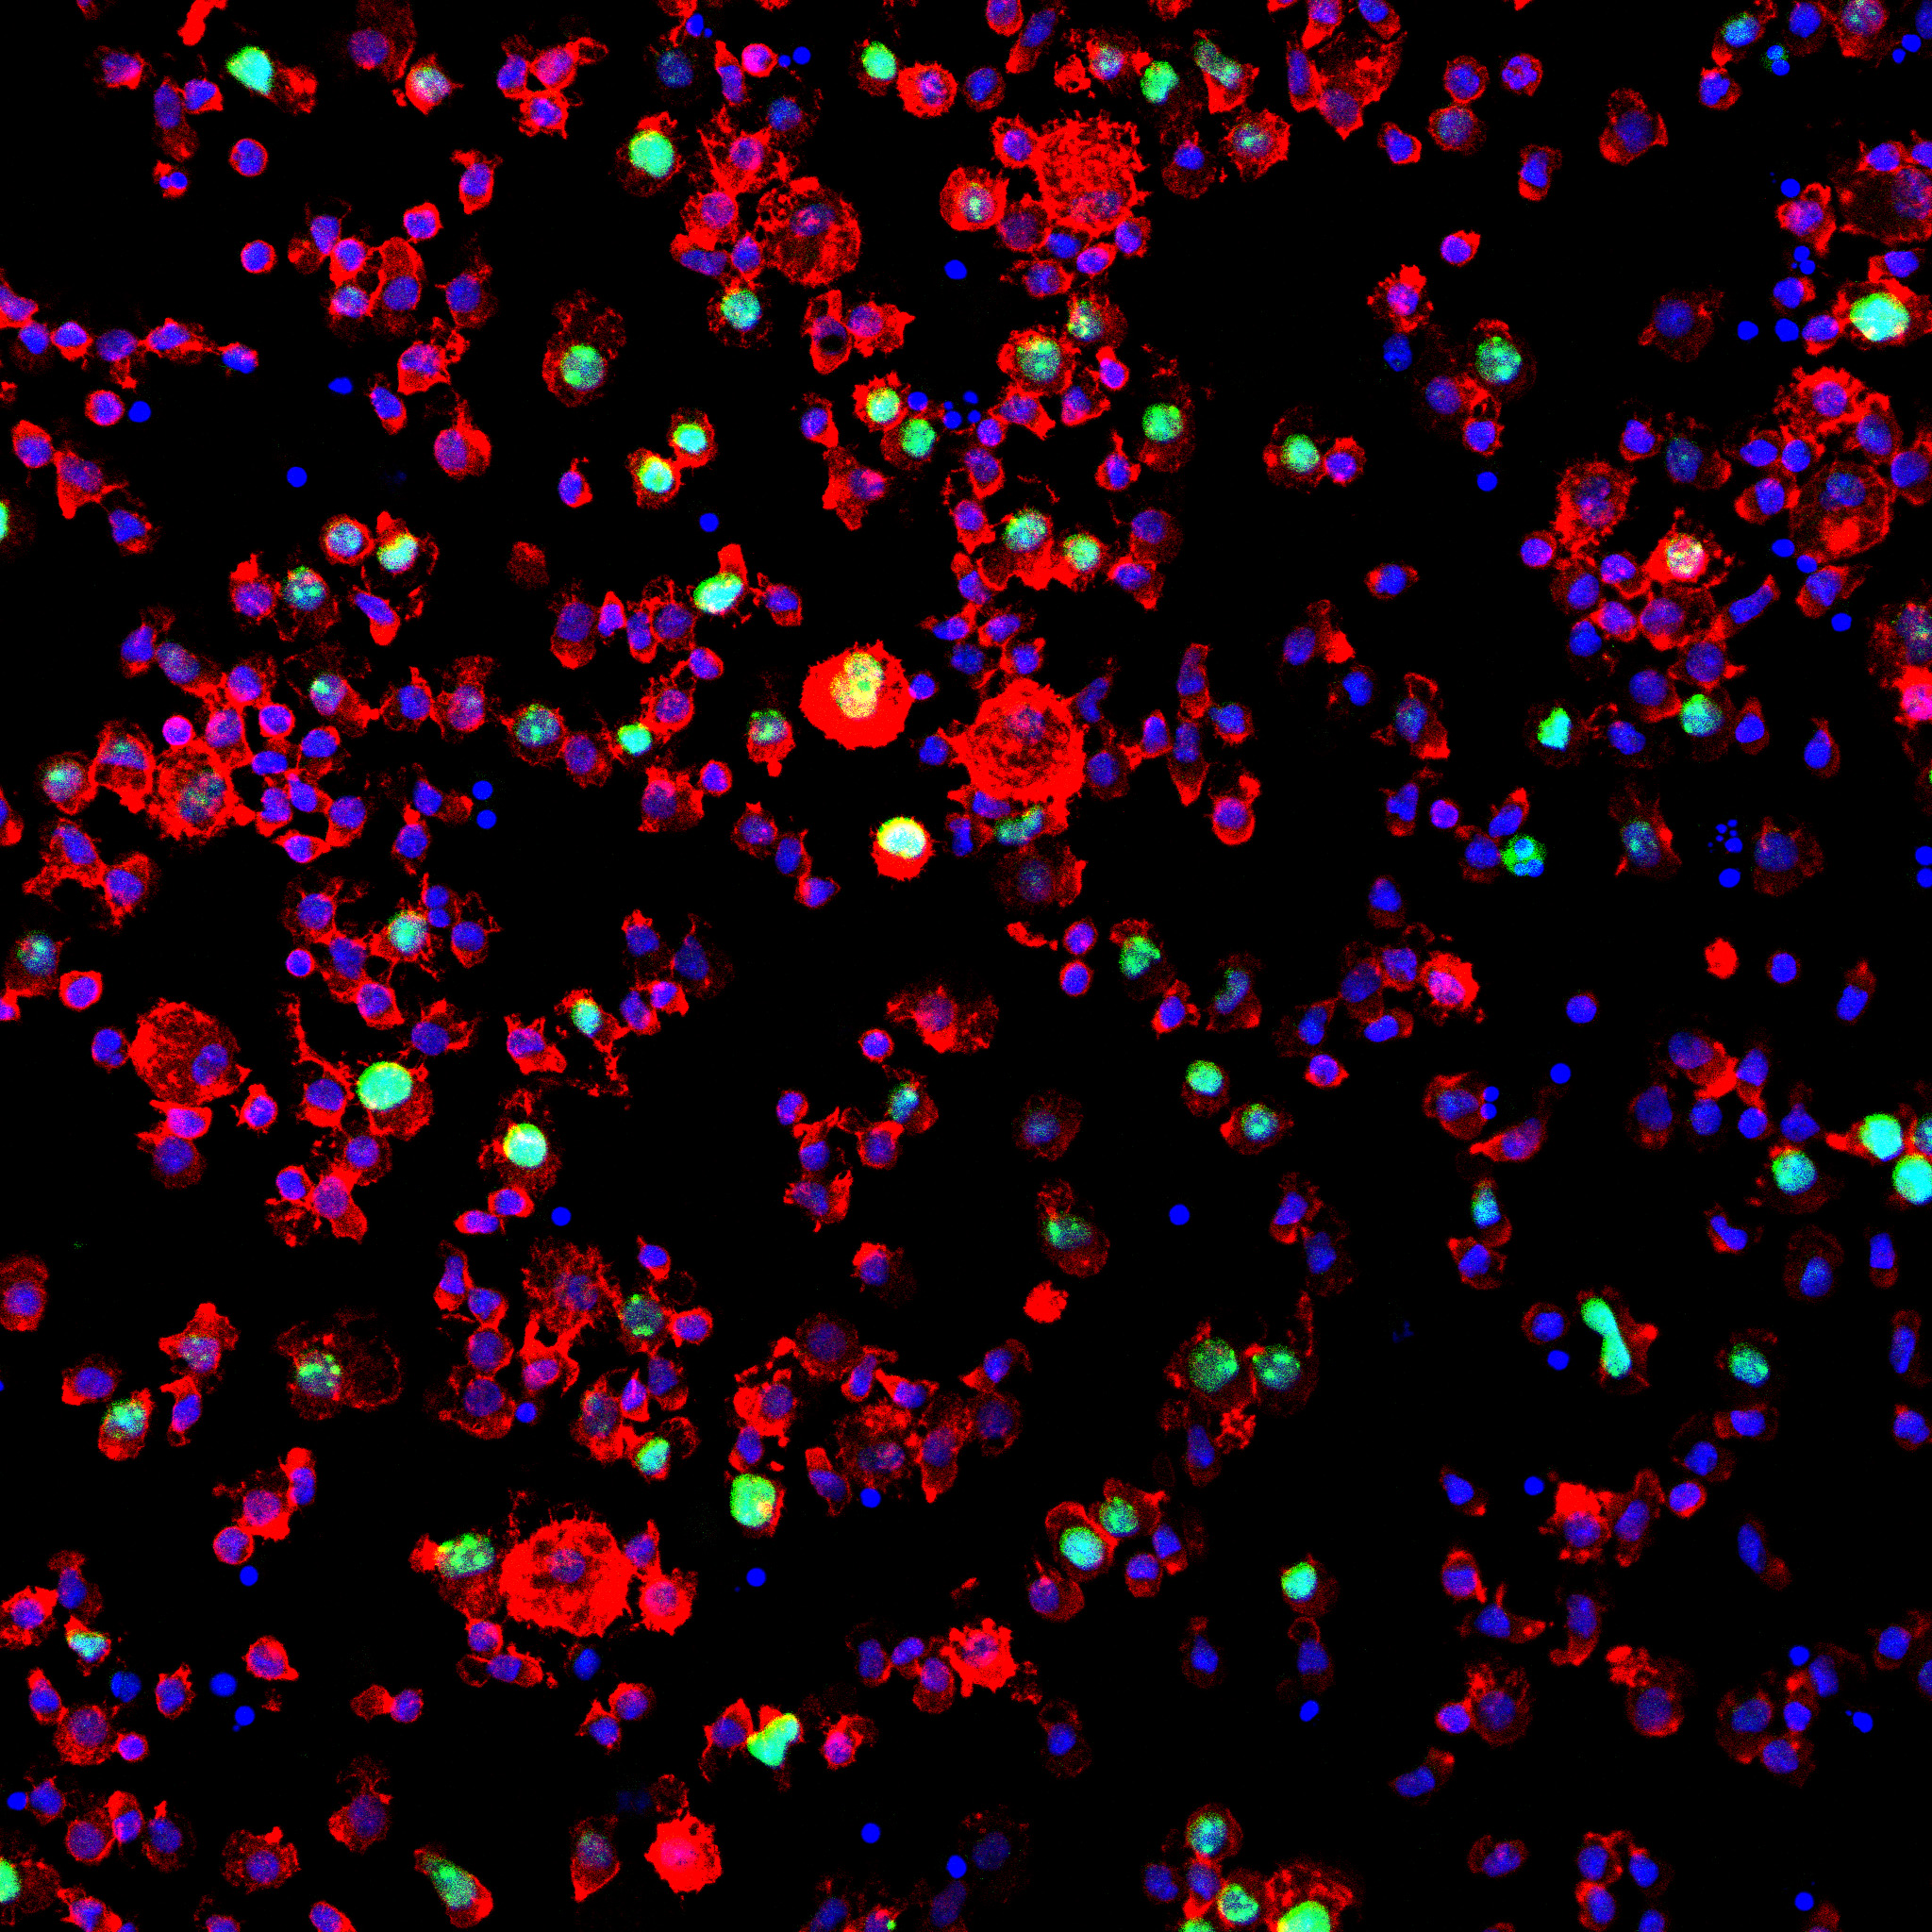

Innowacyjny model finansowania kosztownego leczenia nowotworów złośliwych. Pomysł polega na wykorzystaniu obrazów prawdziwych komórek nowotworowych, przekształceniu ich w dzieła sztuki, a następnie stworzeniu z nich NFT. Pozyskane z akcji środki przeznaczane są na leczenie osób, walczących z przedstawionymi na zdjęciach nowotworami .